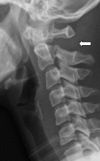

To describe the biomechanically relevant anatomy of the Axis vertebra and the load transfer patterns within the bone, and on that basis, to postulate its mechanism of injury, a literature review was conducted of the anatomy and biomechanics of Axis fractures. Two hypotheses have been presented: the internal gear hypothesis and the leaf spring hypothesis. Both are based on the trabecular anatomy of the vertebra and its load transmission patterns. The relationship of the Axis with Hangman's injury is also discussed. According to the leaf spring hypothesis, the C2 pedicle corresponds to the shackle in the assembly and constitutes the weak link. The trabecular architecture of the Axis is such that the primary compression of the trabeculae is directed from the superior facet to the C2-3 endplate, with few trabeculae directed to the inferior facet. Along with the trabecular void in this area, this renders the isthmus vulnerable to trauma. The isthmus of the Axis is biomechanically susceptible to injury due to its unique anatomy in relation to the whole cervical spine and the internal load transmission patterns of the bone. The author suggests that in the flexion type of Hangman's injury, the C1-2 posterior ligaments are disrupted and need to be addressed.